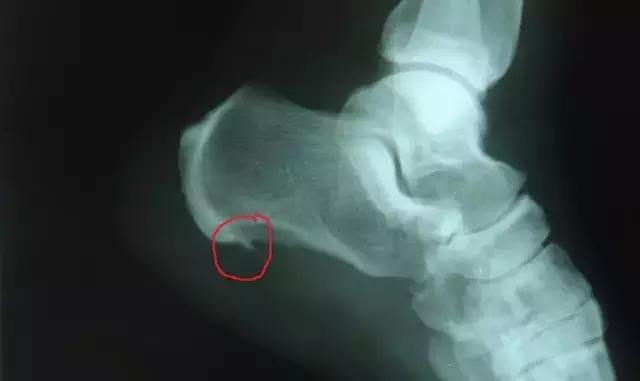

就是我们生活里经常会提到的“骨刺”。

骨刺,就像我们脸上的皱纹,随着年龄的增长,关节软骨的退化,骨刺自然而然就产生了。因此,骨刺不是病,目前的西医教科书里就没有称为“骨刺”疾病诊断。

随着年月渐长,骨关节会逐渐退化,骨头与软组织接触的地方因长期承受压力、拉力、损伤,造成关节间的软骨渐渐失去水分与弹性,使得骨头与骨头发生磨损。

人体为了减小骨头与关节之间的压力,在骨关节边缘上自然而然就会代偿性地增生一部分来减轻这个压力,这是人体为适应力的变化而产生的一种自我保护反应。

骨刺的发生部位以膝关节、跟骨、脊椎等部位为常见。